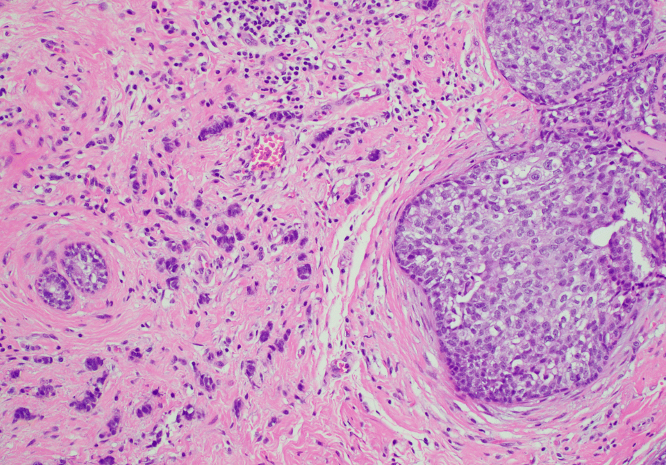

제자리암은 영어로 Carcinoma in situ라고 하며, 말 그대로 ‘제자리에 있는 암’을 의미합니다. 암세포가 생기긴 했지만, 기저막을 뚫지 않아 주변 조직으로 퍼지지 않은 상태를 말합니다. 이 단계에서는 세포가 비정상적으로 변했지만, 혈관이나 림프를 통해 다른 부위로 전이되지는 않습니다.

제자리암과 침윤암의 가장 큰 차이는 ‘퍼짐의 유무’입니다. 제자리암은 세포가 변형되었으나, 그 변화가 한정된 부위에 머무는 상태입니다. 반면 침윤암은 세포가 기저막을 넘어 주변 조직, 림프, 혈관 등으로 퍼진 상태를 말합니다. 따라서 침윤암은 수술, 항암, 방사선 치료 등 적극적 치료가 필요하지만, 제자리암은 비교적 관리 중심으로 접근할 수 있습니다.

제자리암은 건강검진이나 정기 세포검사에서 우연히 발견되는 경우가 많습니다. 대부분 증상이 없기 때문입니다. 예를 들어 자궁경부 제자리암은 자궁경부 세포검사(Pap smear)에서 비정상 세포로 확인되고, 조직검사로 확진됩니다. 유방 제자리암 역시 유방촬영이나 초음파에서 미세석회화 병변으로 나타나 진단됩니다.